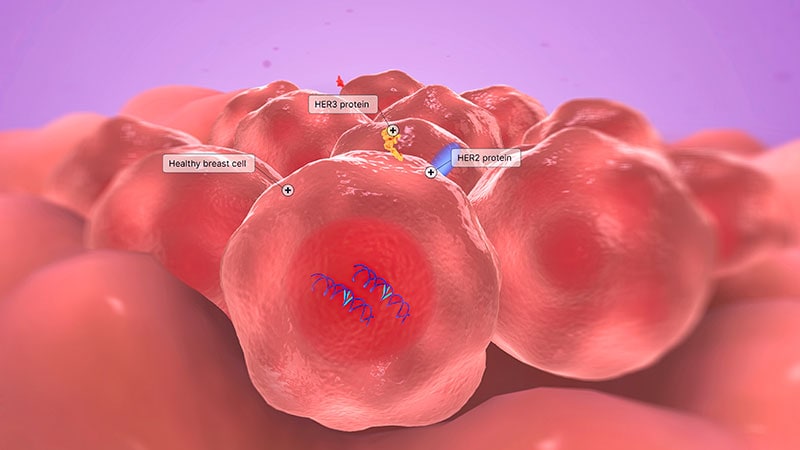

Survival-Toxicity Trade-off With T-DM1 in HER+ Breast Cancer

Trop-2 Drug Conjugate May Trump Chemo in HR+, HER2- BRCA

HER2+ Combo Shows Promise in Breast Cancer Brain Mets